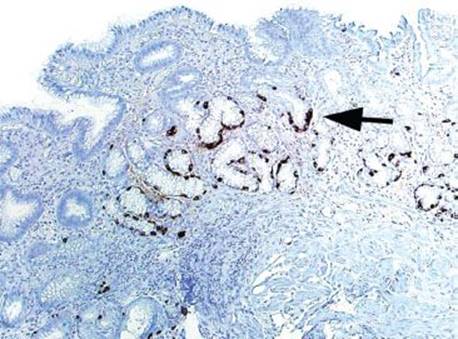

Figure 2.88 Chronic gastritis pattern, linear ECL cell hyperplasia (chromogranin immunostain). The uninhibited gastrin secretion in autoimmune metaplastic atrophic gastritis (AMAG) results in ECL cell hyperplasia (≥5 ECL cells arranged together). This example shows a linear configuration (arrow) of ECL cell hyperplasia&emdash;at least five ECL-consecutive cells arranged in a row.

Answer: By definition, ECL cell hyperplasia refers to five or more ECL cells arranged in a back-to-back configuration, either grouped in a row (linear ECL cell hyperplasia) (Fig. 2.88) or in a cluster (nodular ECL cell hyperplasia) (Fig. 2.89). ECL cell hyperplasia is seen in 33% to 100% of patients with AMAG and is best visualized with a chromogranin immunostain.